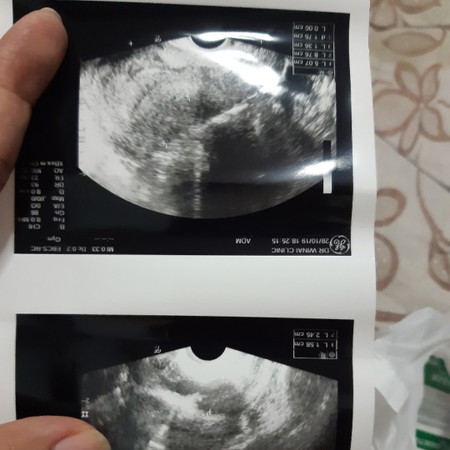

ท้อง 5 วีค หมอซาวไม่พบอะไร รอนัด1 เดือน แม่คนไหนเคยเป็นแบบนี้บ้างคะ

น้องอาจจะยังเล็กไปคะ รอสัก2อาทิตย์คงเห็นคะ ของเราซาวด์ตอน7วีค มีหัวใจเต้นตุ้บๆแล้วคะ